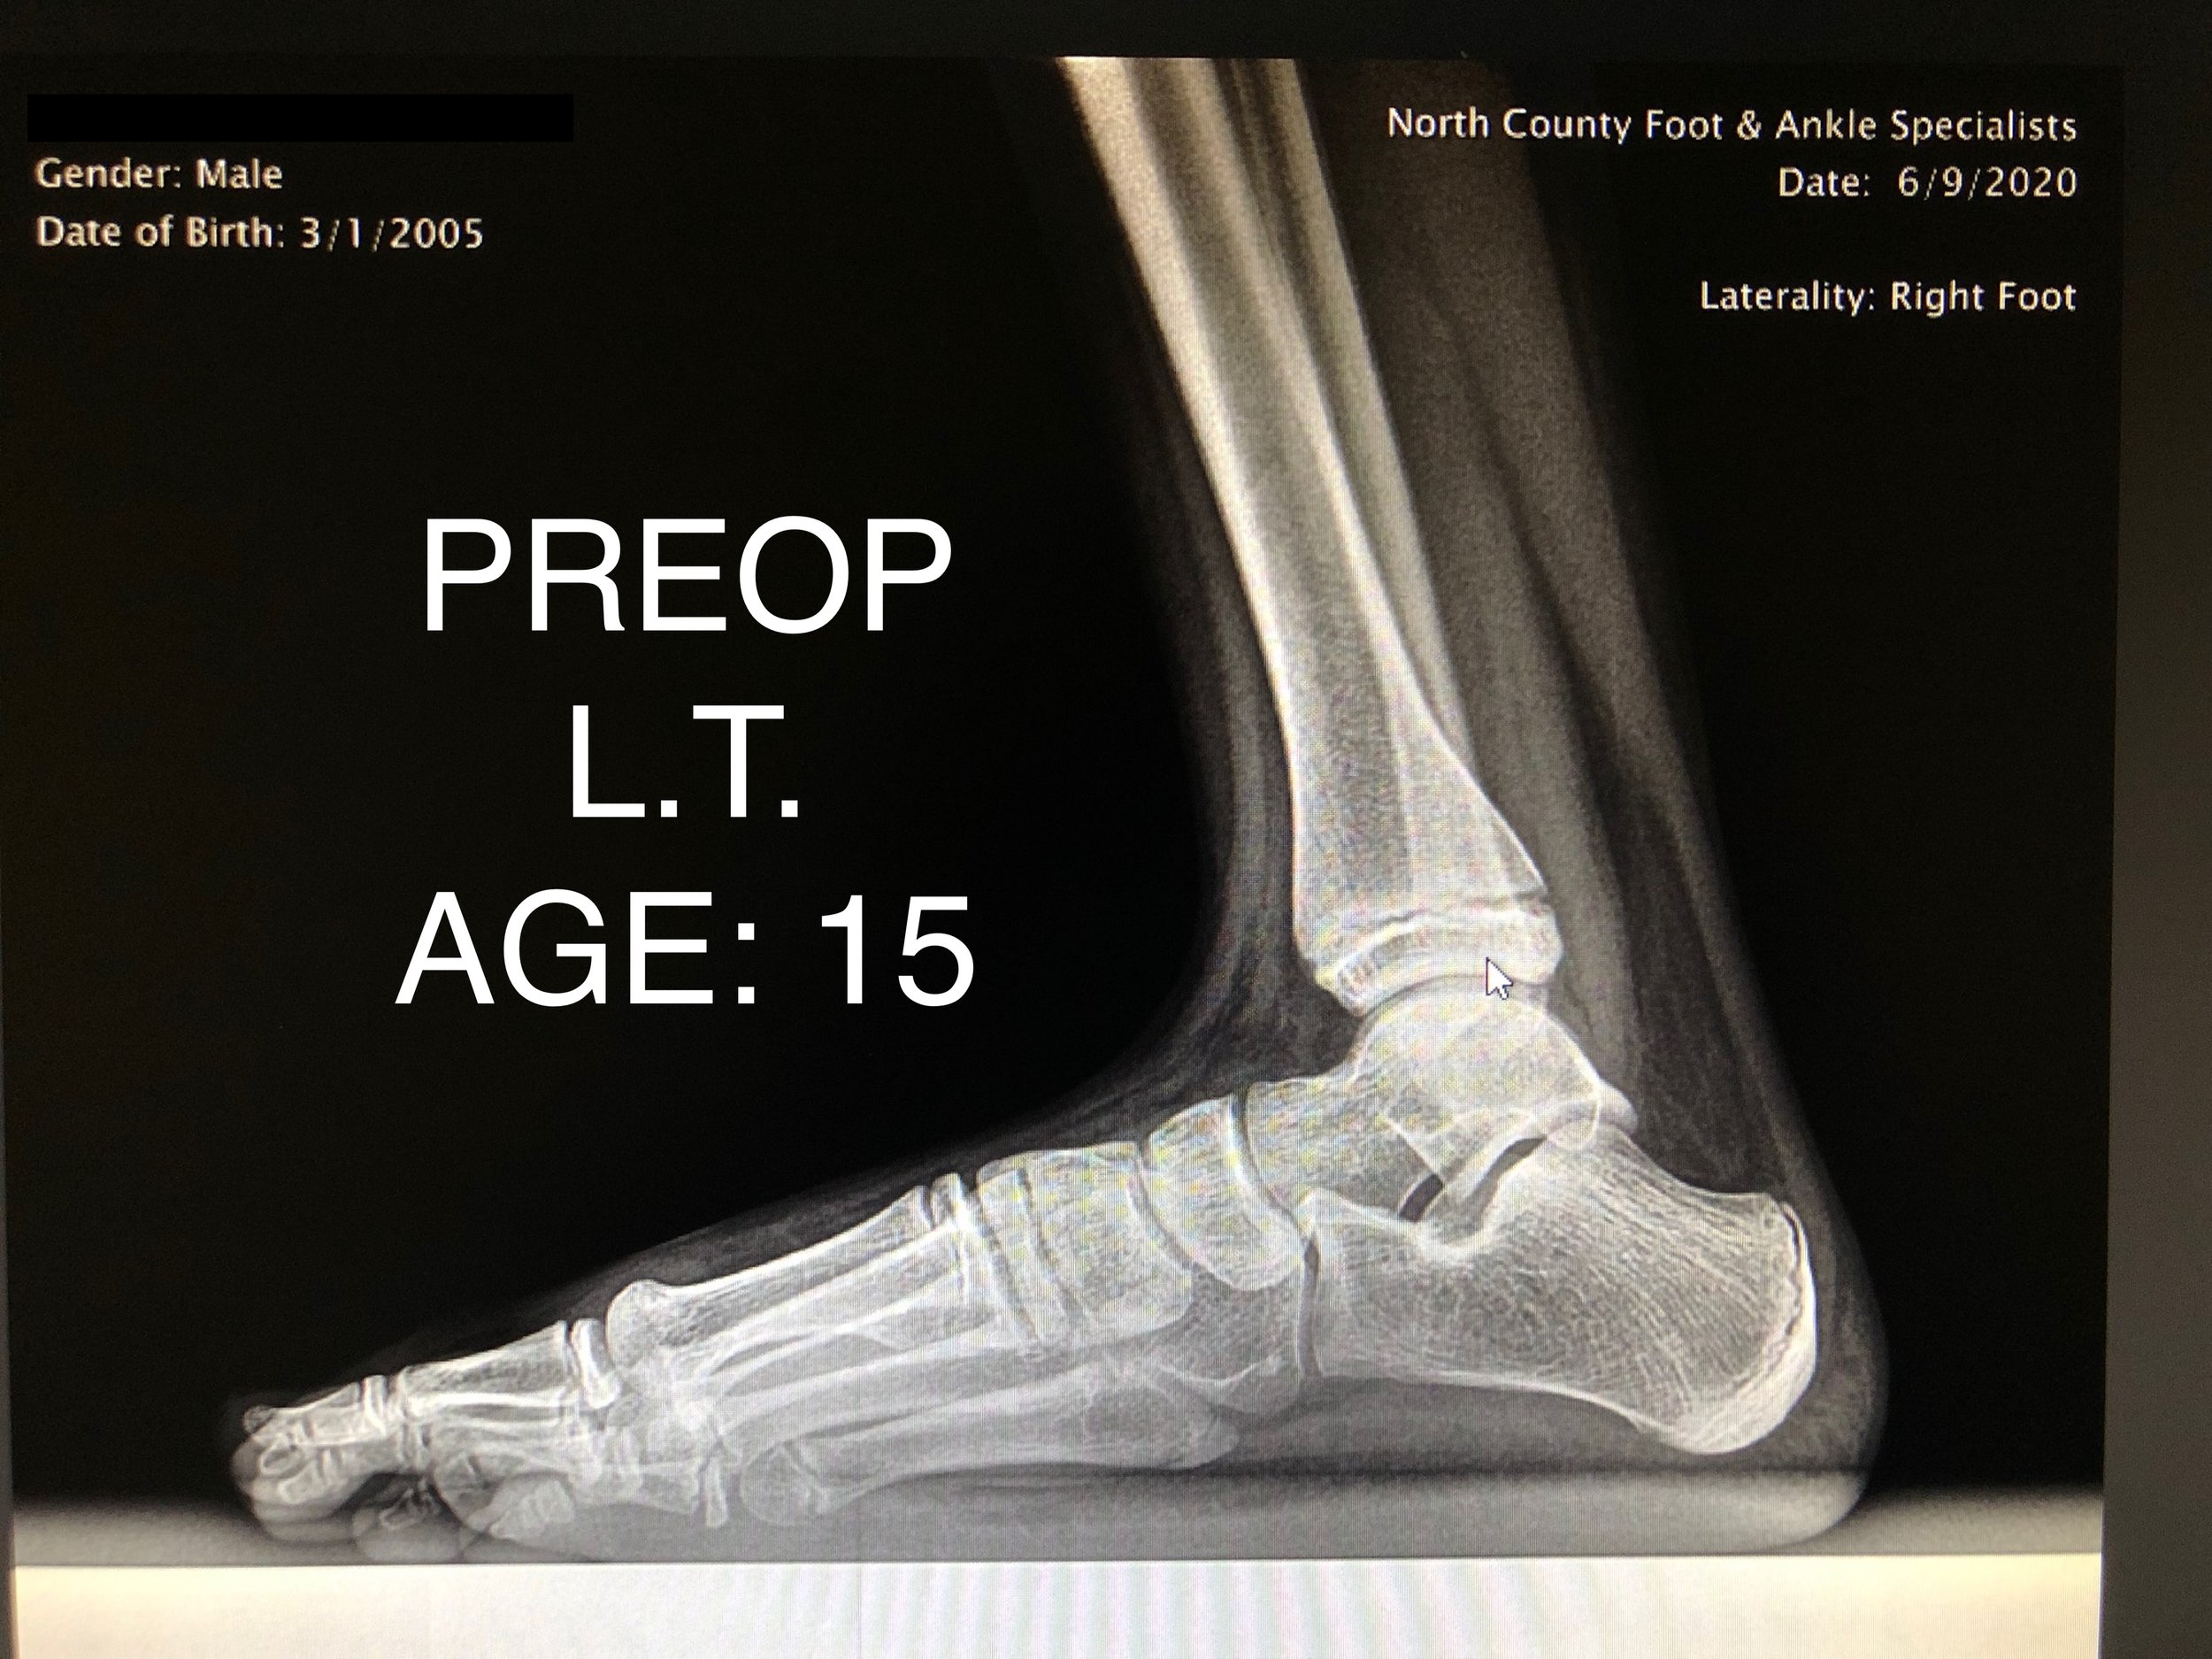

PEDIATRIC FLAT FOOT